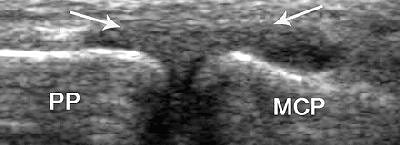

![]() |

| UCL strain in a 32-year-old man. Coronal US scan of the thumb shows diffuse thickening of the UCL (arrows) without a tear. MCP = metacarpal, PP = proximal phalanx. |

"The spectrum of UCL injury includes strain, partial-thickness tear, and full-thickness tear. We outline a simple method of performing (ultrasound) of the thumb and discuss the spectrum of common acute disorders encountered with particular emphasis on UCL injuries," they wrote.

In their sample of 32 patients, ultrasonography was performed with the hand placed flat on a table. A 12- to 23-MHz linear probe was slid from the second finger onto the first metacarpophalangeal joint to obtain either a transverse image of the UCL or a longitudinal one.

In general, the UCL tear is considered displaced when it is retracted or folded on itself. It will also move proximal to the adductor aponeurosis, which creates the appearing of a yo-yo on a string, according to the authors. The yo-yo portion is the torn, displaced UCL.